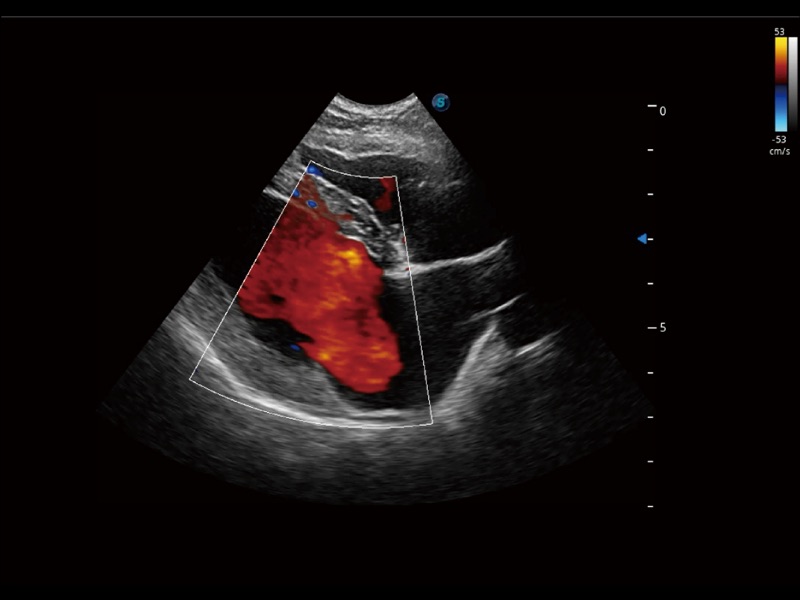

(犬)髂动脉血流

(犬)胎儿主动脉弓立体血流